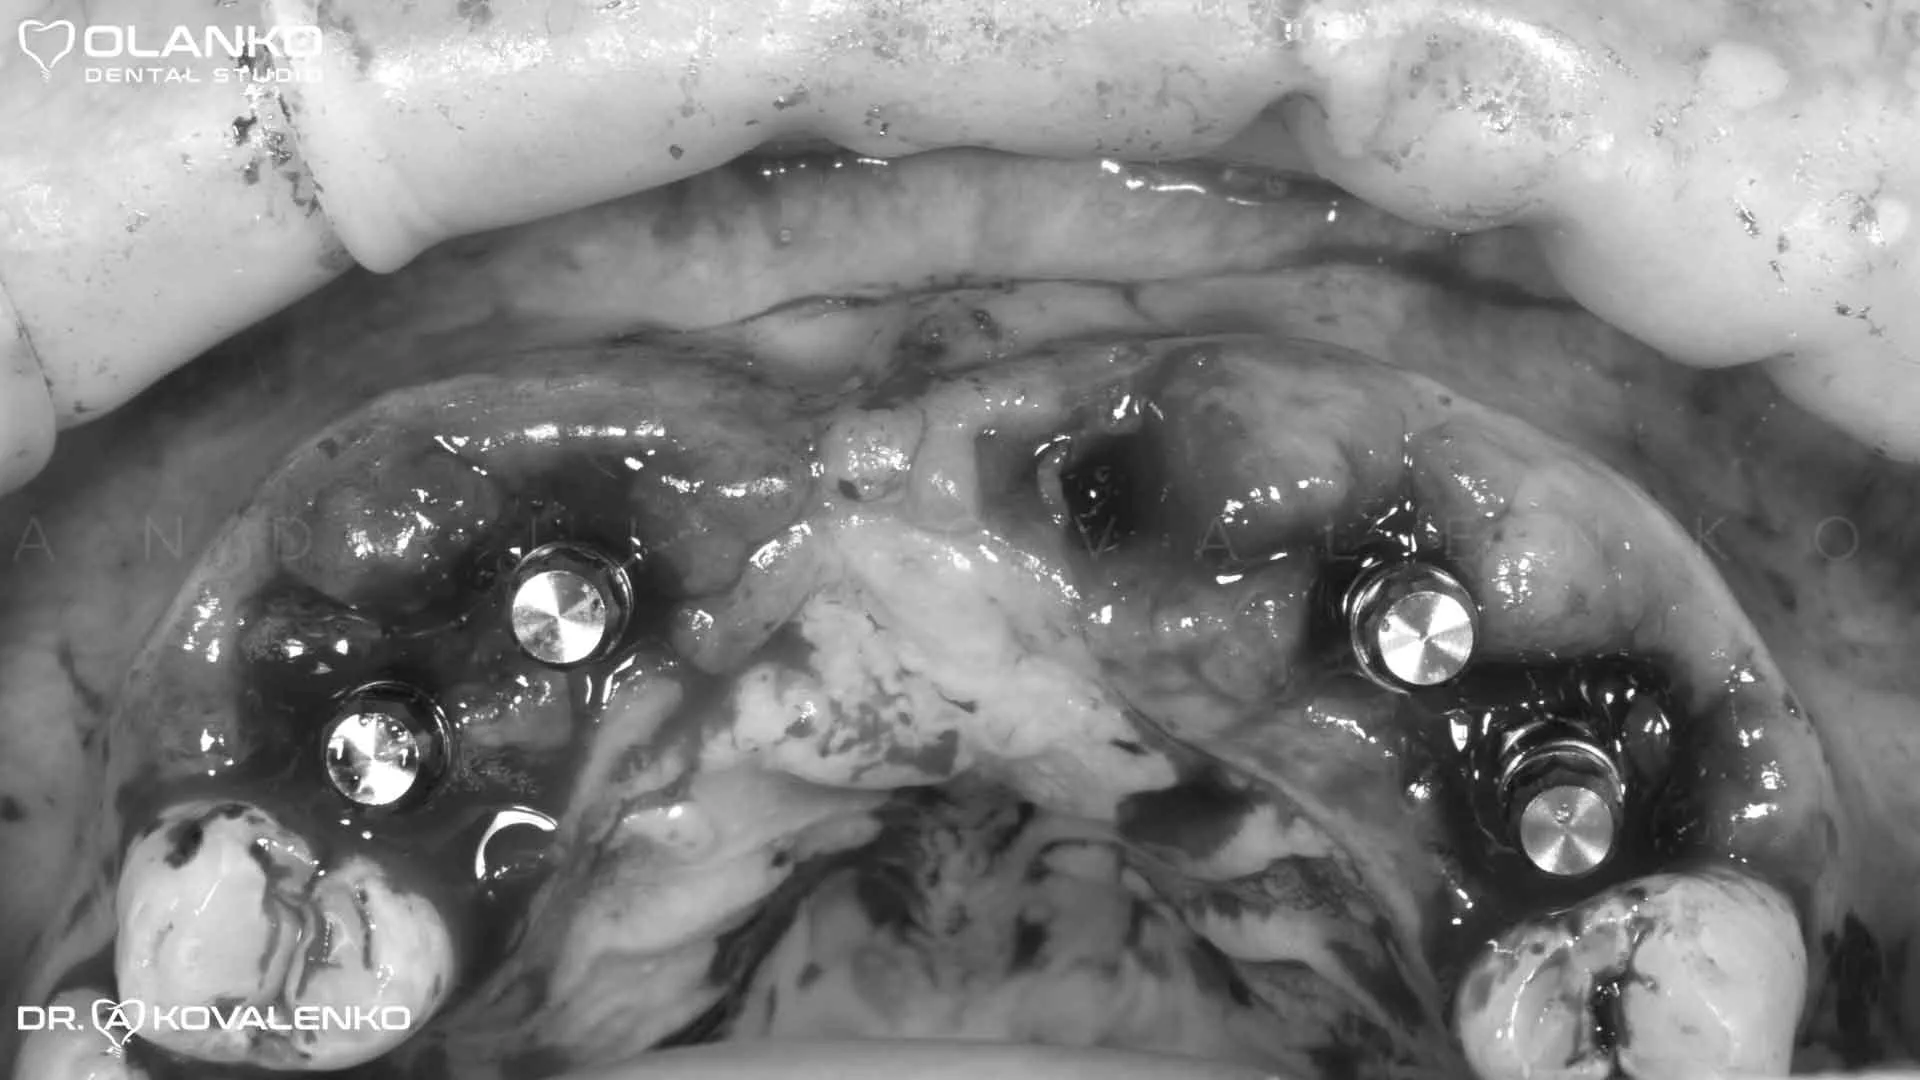

Фото момент установки зубных имплантатов

Клинический случай 8 имплантация зубов